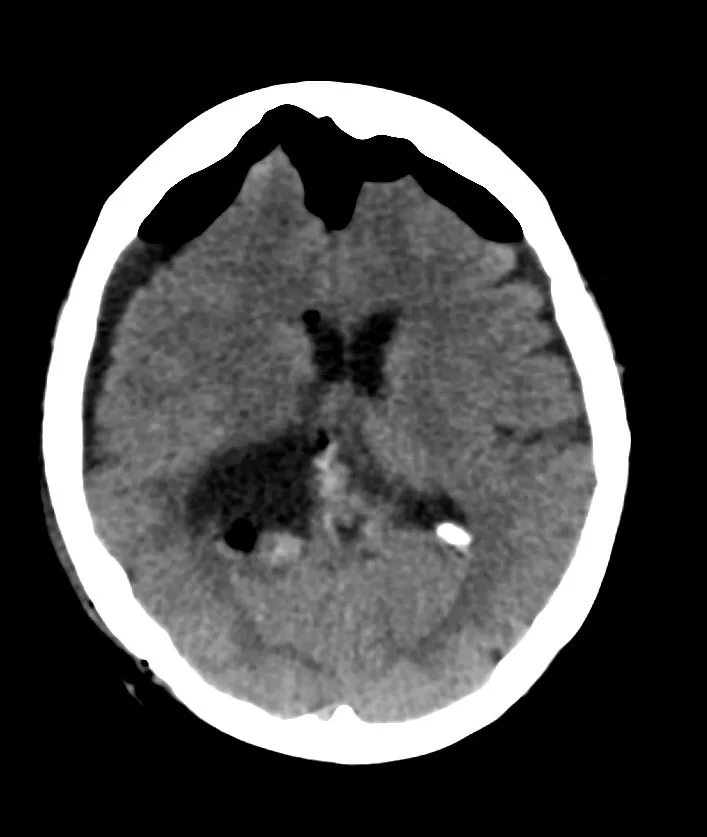

Η μετεγχειρητική αξονική τομογραφία εγκεφάλου δείχνει πλήρη αφαίρεση της βλάβης. Η ιστολογική εξέταση ανέδειξε μηνιγγίωμα WHO I.

Η ασθενής ανάρρωσε πλήρως, και εξήλθε του νοσοκομείου την 6η μετεγχειρητική ημέρα χωρίς καμία επιπλοκή.